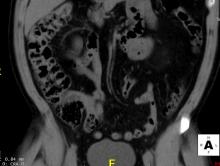

In 2009, the Centers for Medicare and Medicaid Services (CMS) halted reimbursement for so-called “virtual colonoscopy” for routine colon-cancer screening in asymptomatic patients, in part due to concerns over how this procedure, computed tomography colonography (CTC), was being used in the elderly population.